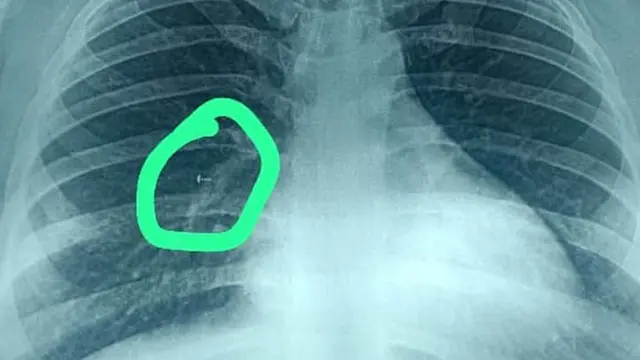

त्यांनी यावर औषधं घेतली, मात्र त्यांना बरं वाटत नव्हतं. मग त्या श्वसनाशी संबंधित तज्ज्ञाकडे गेल्या. त्यांचं सीटी स्कॅन करण्यात आलं आणि त्यात असं आढळून आलं की त्यांच्या फुफ्फुसात काहीतरी वस्तू आहे. त्यांच्या छातीचा एक्स रे काढण्यात आला आणि त्यात ही वस्तू काय आहे हे दिसून आलं.

डॉक्टरांनी वर्षा यांच्या श्वासनलिकेत आत एक छोटा कॅमेरा असलेला शस्त्रक्रियेचा चिमटा सोडला. मात्र त्यातून ही फुफ्फुसात गेलेली वस्तू काढता आली नाही. त्यानंतर त्यांना डॉ. जश यांच्याकडे पाठवण्यात आलं.